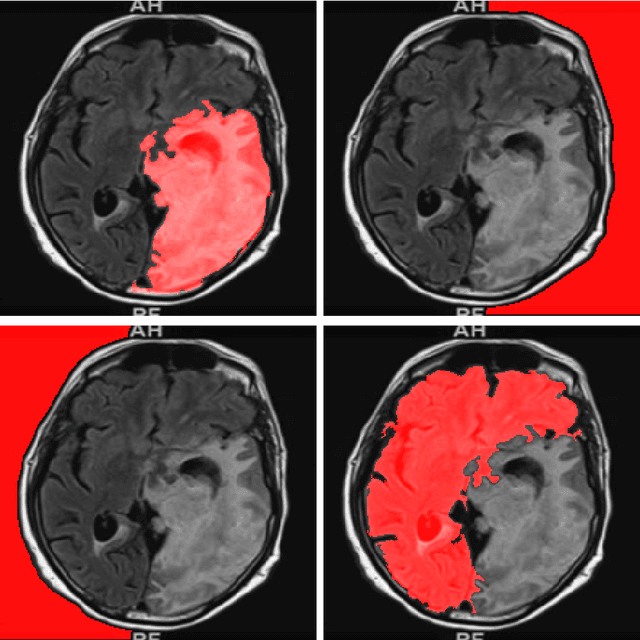

Abstract:Purpose: Lesion segmentation in medical imaging is key to evaluating treatment response. We have recently shown that reinforcement learning can be applied to radiological images for lesion localization. Furthermore, we demonstrated that reinforcement learning addresses important limitations of supervised deep learning; namely, it can eliminate the requirement for large amounts of annotated training data and can provide valuable intuition lacking in supervised approaches. However, we did not address the fundamental task of lesion/structure-of-interest segmentation. Here we introduce a method combining unsupervised deep learning clustering with reinforcement learning to segment brain lesions on MRI. Materials and Methods: We initially clustered images using unsupervised deep learning clustering to generate candidate lesion masks for each MRI image. The user then selected the best mask for each of 10 training images. We then trained a reinforcement learning algorithm to select the masks. We tested the corresponding trained deep Q network on a separate testing set of 10 images. For comparison, we also trained and tested a U-net supervised deep learning network on the same set of training/testing images. Results: Whereas the supervised approach quickly overfit the training data and predictably performed poorly on the testing set (16% average Dice score), the unsupervised deep clustering and reinforcement learning achieved an average Dice score of 83%. Conclusion: We have demonstrated a proof-of-principle application of unsupervised deep clustering and reinforcement learning to segment brain tumors. The approach represents human-allied AI that requires minimal input from the radiologist without the need for hand-traced annotation.